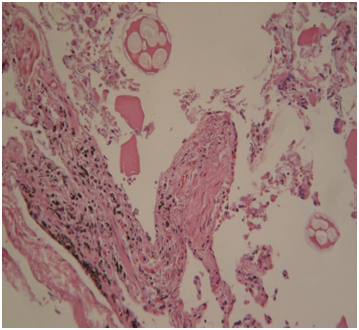

The determination of chemical substances present in the drowning medium could be a complementary tool in the forensic investigation.1,2 Referring to this, both strontium (Sr) and silicon (Si) have proven to be interesting in the diagnosis of drowning (D), in addition to the histological and SEM plankton research in lower airways (Figure 1,Figure 2)(Table 1).

Figures 1 Plankton bolus in the alveolar duct (drowning in freshwater), ordinary (Figure A) and polarized light (Figure B) (EE, 480X).

Histology: Acute emphysema was the prominent observation; edema and hemorrhages were also present.4 In 9 cases (Figures 3-6), exogenous material in the airways, comprehensive of planktonic boli in the lower branches, clearly demonstrable at polarization microscope (and possibly confirmable at SEM’s elemental analysis with EXD). Zoo- and phytoplankton have been better identified in the UV microscope. It is mandatory to differentiate the planktonic material from gastric content, regurgitated and aspirated (Figure 7 & 8).